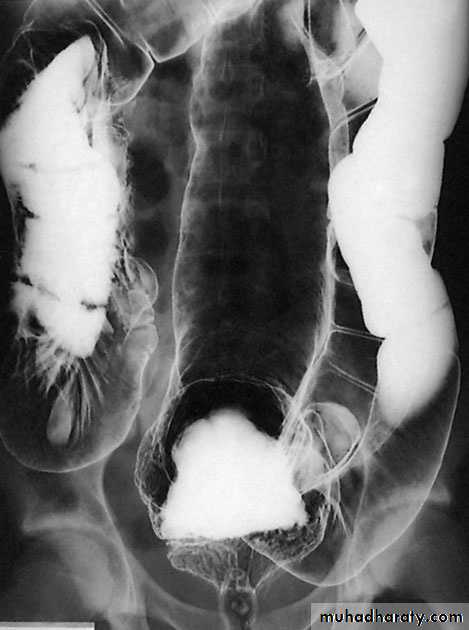

InvestigationImagingAs there is an enlarged rectum, often with distension of the colon over a variable length, a radiograph should be taken without prior bowel preparation, using a small quantity of water-soluble contrast to prevent barium impaction. There is usually gross faecal loading of the enlarged rectum and colon and, when a contrast examination is carried out, the width of the colon measured at the pelvic brim is usually more than 6.5 cm.

Barium enemaThe principal signs are :• loss of haustration, especially in the distal colon;• mucosal changes caused by granularity;• pseudopolyps;• in chronic cases, a narrow contracted colon.